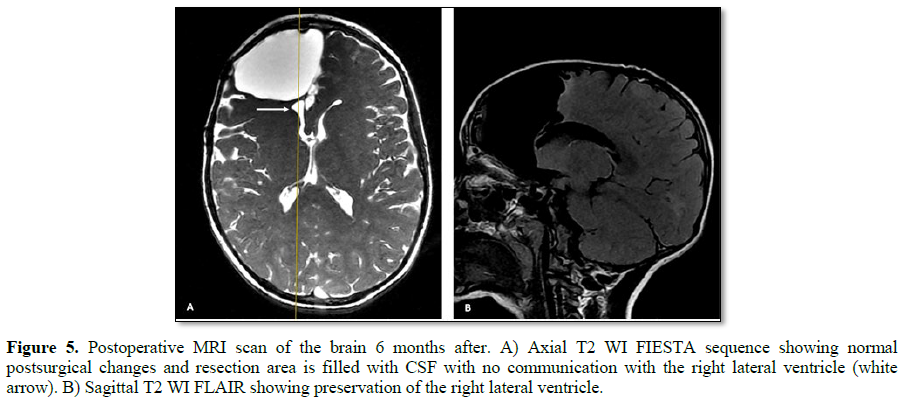

He underwent a frontal lobectomy with intraoperative ECoG and placement of subdural grids (Figure 3). During surgery the intracranial monitoring demonstrated the localization of the epileptogenic zone near to the supplementary motor area. When performing the resection of the affected frontal lobe the preservation of the right lateral ventricle was achieved. The postoperative course was uneventful. Cerebral tissue was sent to neuropathology for examination and the final pathological diagnosis of resected right frontal lobe was FCD Type IIa (Figure 4) with polymicrogyria and pachygyria. His follow-up brain MRI, taken 6 months after his surgery, indicated successful resection of the lesion, resect area is filled with cerebro-spinal fluid (CSF) and the right lateral ventricle is preserved (Figure 5). The patient remains Engel Class I and showed an improvement in language and cognition. The patient goes to a follow-up clinic, 18 months after surgery, the child understands three languages (Spanish, Portuguese and English), free of seizure, Engel 1A.